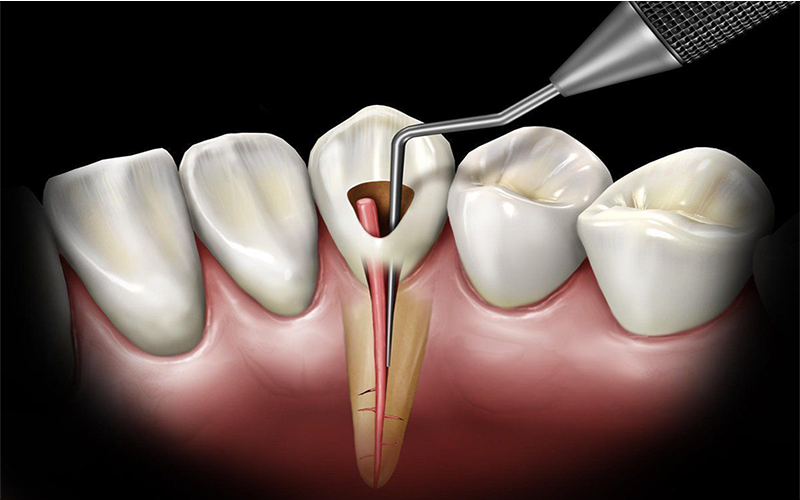

مراحل درمان ریشه دندان:

برداشتن پالپ: دندانپزشک از طریق ایجاد یک حفره کوچک در تاج دندان، به پالپ دسترسی پیدا میکند و آن را به همراه اعصاب و عروق خونی آسیبدیده از کانالهای ریشه خارج میکند.

تمیز کردن و ضدعفونی: پس از برداشتن پالپ، کانالهای ریشه با دقت تمیز و ضدعفونی میشوند تا هرگونه باکتری یا باقیماندههای عفونی از بین برود.

پر کردن کانالها: در مرحله بعد، کانالهای تمیز شده با مواد مخصوصی به نام گوتاپرکا پر میشوند تا از ورود مجدد باکتریها جلوگیری شود.

مراحل انجام درمان ریشه دندان